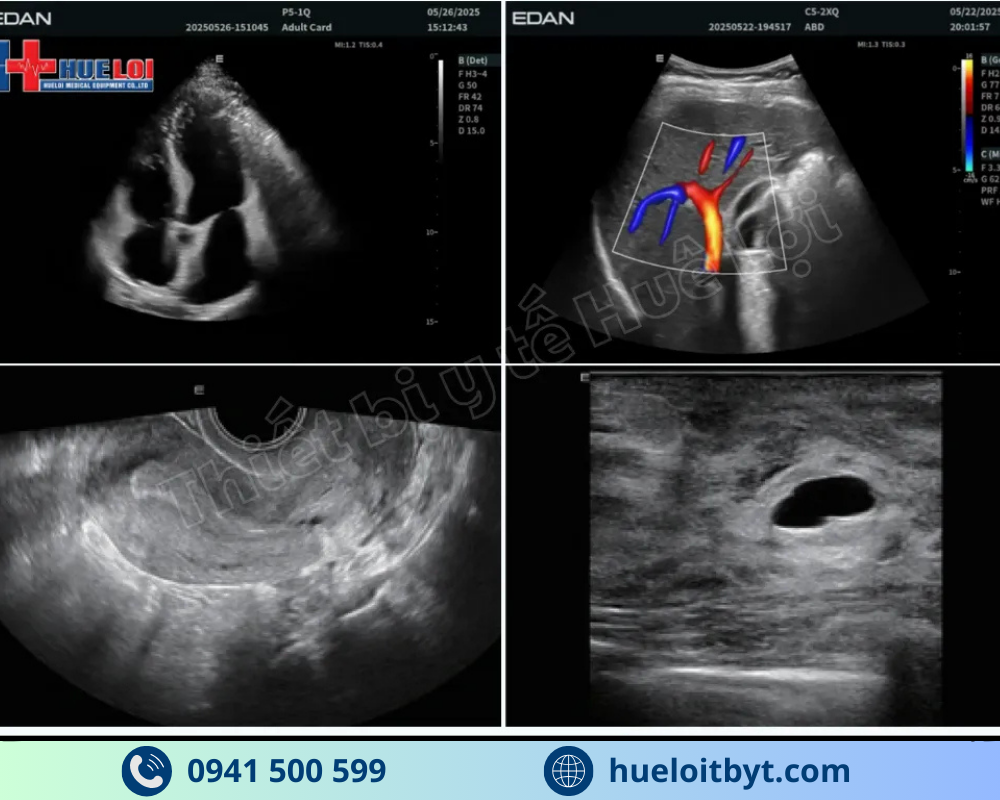

Với mức đầu tư vô cùng hợp lý, mức giá của EDAN LX85 ở thời điểm hiện tại chỉ nằm trong khoảng hơn 350 triệu đồng cho cấu hình 3 đầu dò, máy siêu âm bàn đẩy EDAN LX85 đã phá vỡ mọi quy chuẩn trong phân khúc. Điểm nổi bật nhất phải kể đến là máy sở hữu những công nghệ cao cấp vốn chỉ có trên các hệ thống đắt tiền hơn nhiều, như công nghệ đàn hồi mô Shear Wave giúp đánh giá trực quan độ cứng tổn thương, công nghệ vi mạch Micro-Flow, và đặc biệt là công nghệ e-Live giúp tái tạo khuôn mặt thai nhi một cách tự nhiên và sắc nét. Sự kết hợp giữa mức giá cực tốt và hàng loạt tính năng chuyên sâu này đã định vị EDAN LX85 là một trong những hệ thống siêu âm bàn đẩy đáng đầu tư nhất trong phân khúc dưới 500 triệu đồng hiện nay.

Được nghiên cứu phát triển chuyên biệt để tối ưu hóa quá trình bác sĩ thăm khám trên lâm sàng, hệ thống Siêu âm Chẩn đoán Acclarix LX85 hướng đến việc cung cấp giải pháp chẩn đoán chính xác với chất lượng hình ảnh vượt trội, thuận tiện quy trình làm việc và vận hành thân thiện với người dùng.

Máy siêu âm Edan LX85 ứng dụng nhiều công nghệ cải thiện chất lượng hình ảnh tiên tiến, cho phép hiển thị thai nhi sắc nét, chi tiết và chân thực ngay từ những tuần thai sớm. Nhờ độ phân giải cao và khả năng xử lý hình ảnh vượt trội, LX85 giúp bác sĩ sản phụ khoa dựng hình khuôn mặt thai nhi vô cùng sắc nét và tự nhiên, ứng dụng AI thông minh giúp tự động xóa những phần có thể che khuôn mặt em bé như nhau thai và tử cung, hỗ trợ chẩn đoán chính xác các bất thường trong thai kỳ. Đây là giải pháp siêu âm hiện đại, mang lại sự an tâm tối đa cho mẹ bầu và bác sĩ trong suốt hành trình theo dõi sản khoa.

Cùng với những ưu việt về phần cứng, máy siêu âm bàn đẩy EDAN thế hệ mới còn được tích hợp công nghệ siêu âm Micro-Flow (Microvascular Flow Imaging) là công nghệ Doppler tiên tiến, giúp phát hiện vi mạch nhỏ có dòng chảy chậm mà siêu âm Doppler truyền thống khó quan sát. Kỹ thuật này không cần dùng chất cản quang nhưng vẫn cho hình ảnh mạch máu sắc nét, hỗ trợ chẩn đoán chính xác trong siêu âm mạch, gan, thận, vú, sản phụ khoa. Với ưu điểm an toàn, độ nhạy cao và hình ảnh trực quan sắc nét, Micro-Flow Imaging ngày càng được ứng dụng rộng rãi trong siêu âm lâm sàng hiện đại.